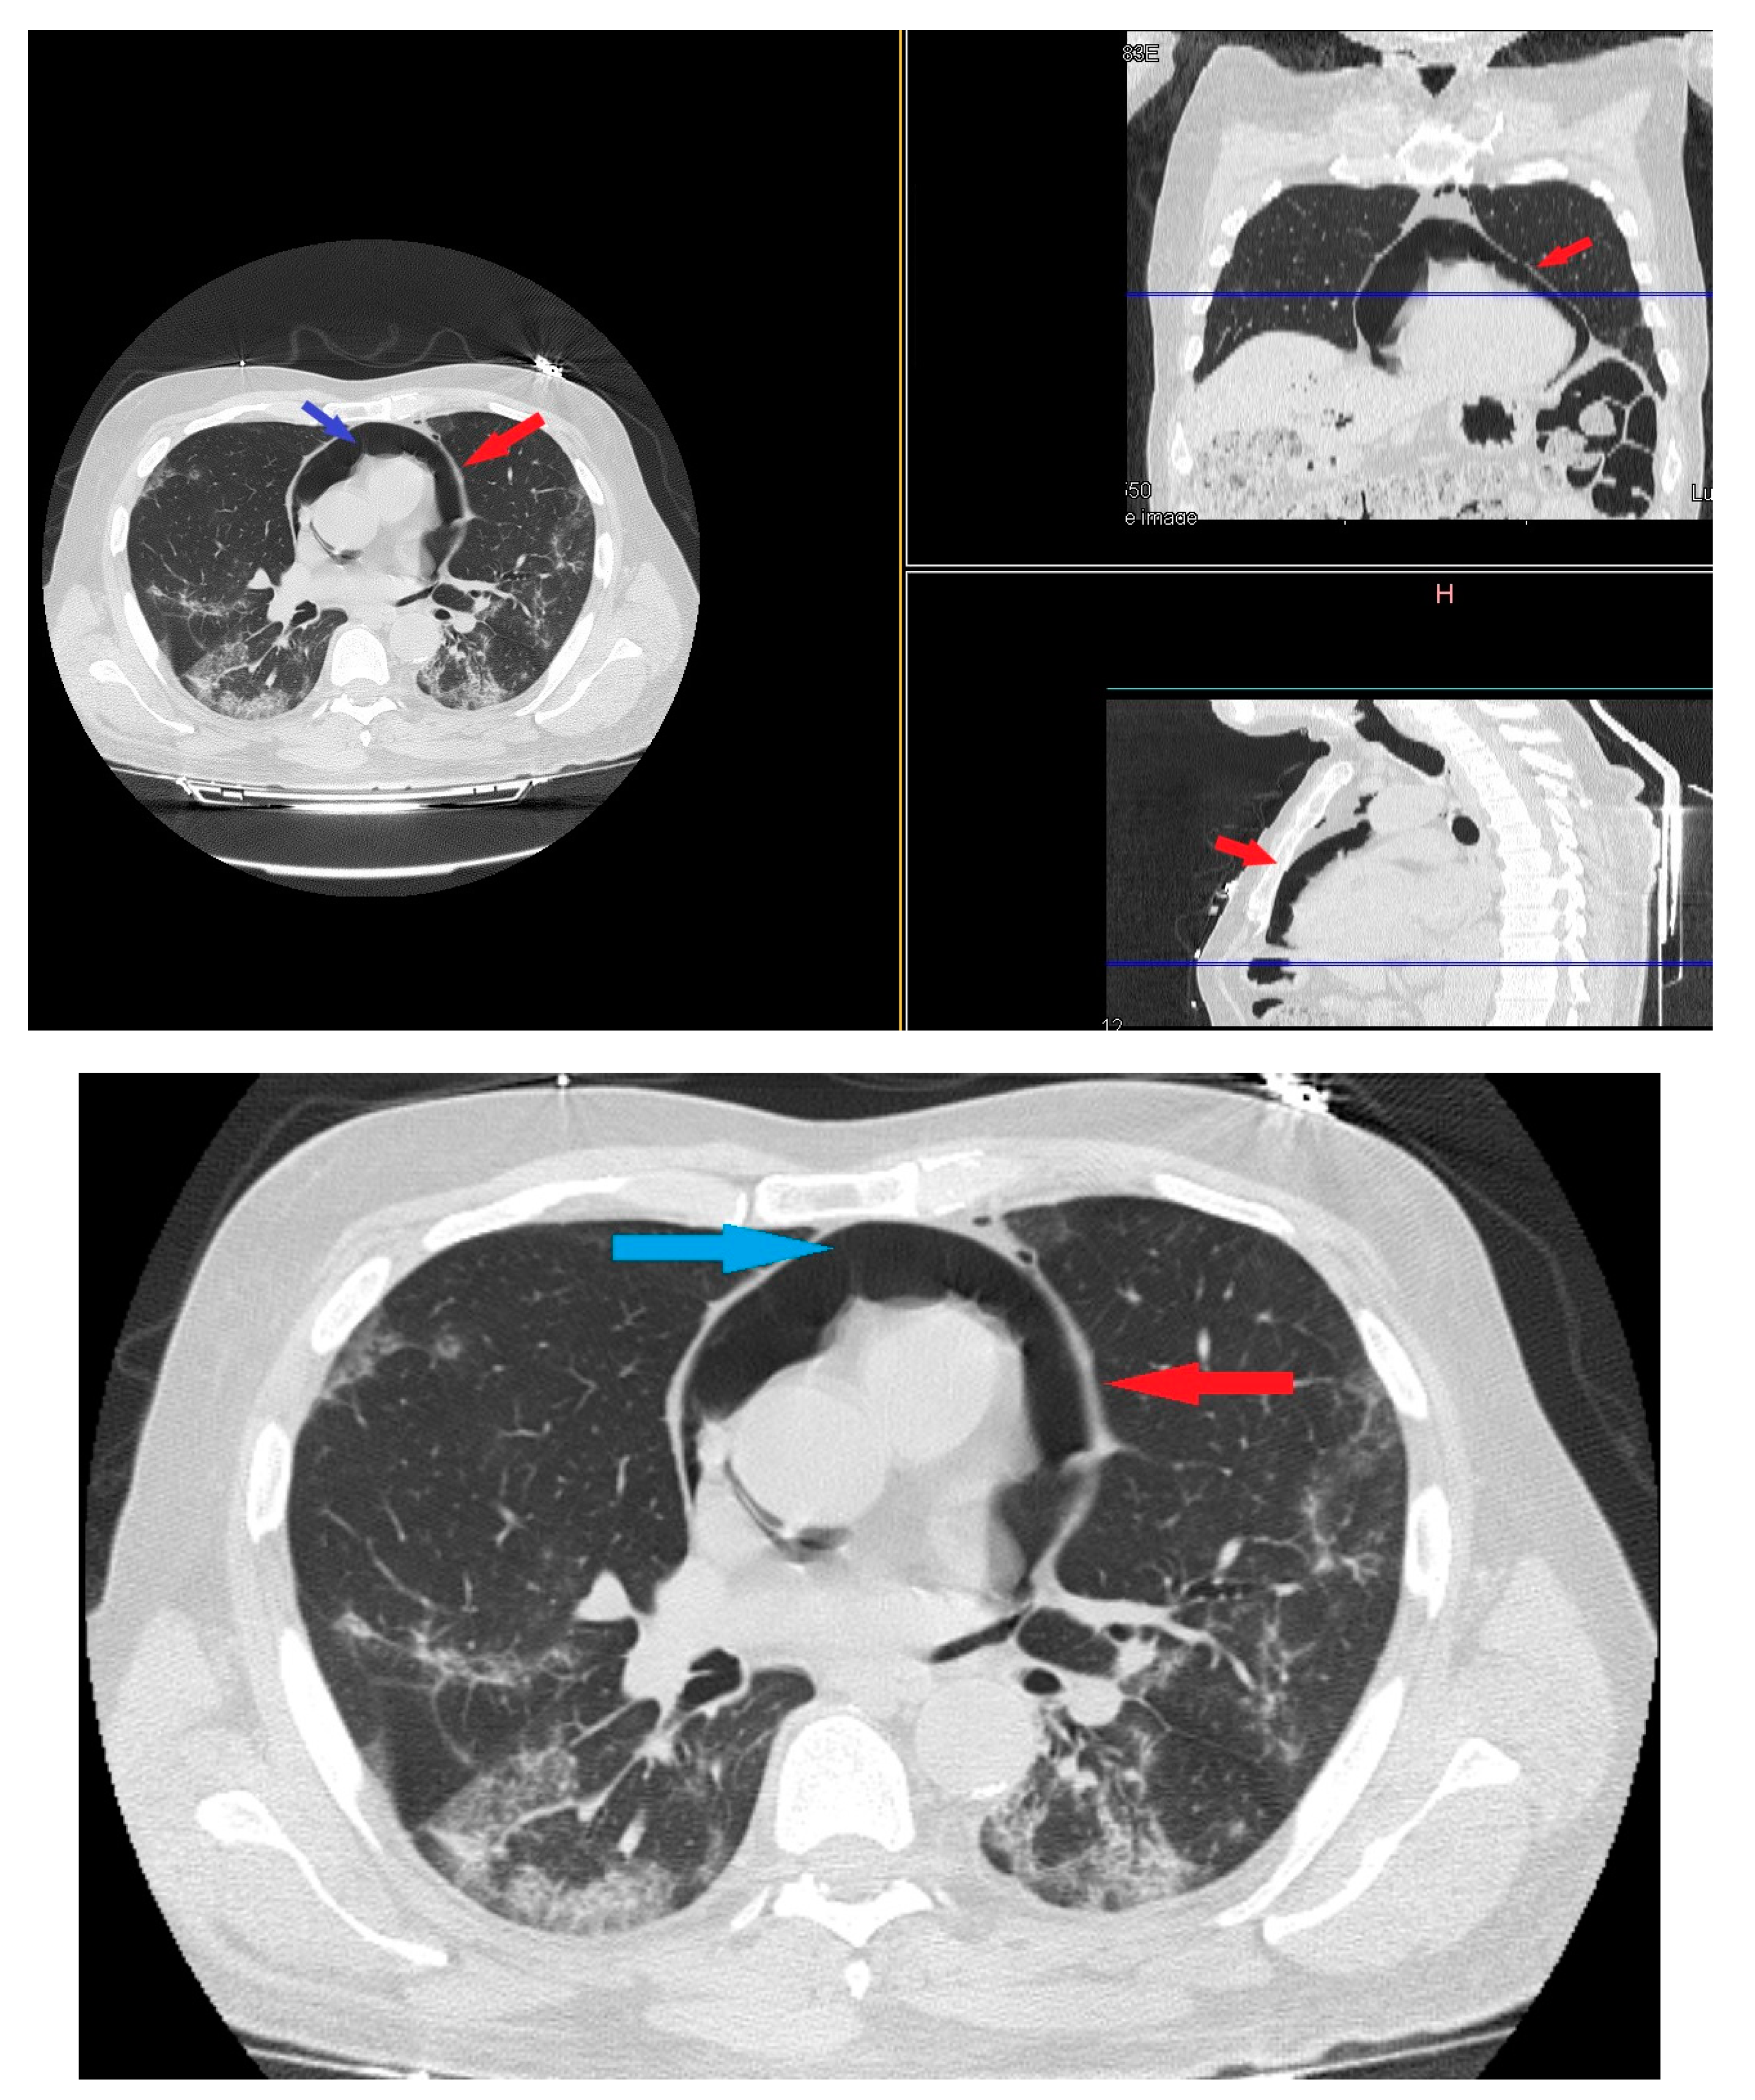

The high-resolution computed tomography scan (HRTC) made on admission (Figure 1) revealed large consolidations and bilateral ground glass opacities (GGO) areas such as progressive Covid pneumonia scored with 11/20 on Total severity score (TSS) [7].

Figure 1. HRTC performed on admission with large consolidations and bilateral ground glass opacities (GGO) TSS 11/20.